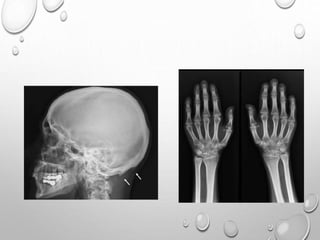

RADIOLOGY

HEAD

LARGE CRANIUM , THOUGH DECREASED AP DIAMETER –

BRACHYCEPHALY

LIMBS

UL> LL

RHIZOMELIC TYPE

METAPHYSIS …..SPLAYING , CUPPING

GENU VERUM

TRIDENT HAND

TIBIA , ULNA ARE MORE SHORTENED THAN FIBULA , RADIUS

V SHAPED NOTCH IN GROWTH PLATE

SHORT , TUBULAR LONG BONES OF HAND AND FEET

FINGERS ARE OF SAME LENGTH

• 1. DYSPLASTIC OR SQUARE

ILIAC BONES

2. NARROW SACRO-SCIATIC

NOTCHES

3. FLAT BILATERAL

ACETABULAR ROOFS

4. SHORT BOTH FEMORAL

NECKS

5. CHAMPAGNE GLASS-

SHAPED PELVIC CAVITY